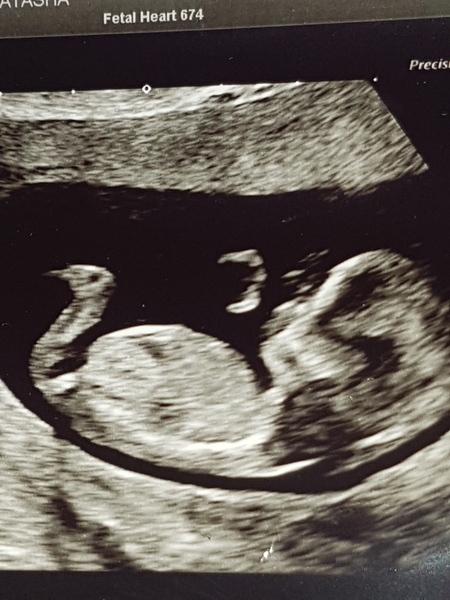

Graciesmummy · 19/11/2019 07:40

Would anyone be able to take a guess using nub theory at the gender on my 12 + 3 scan picture